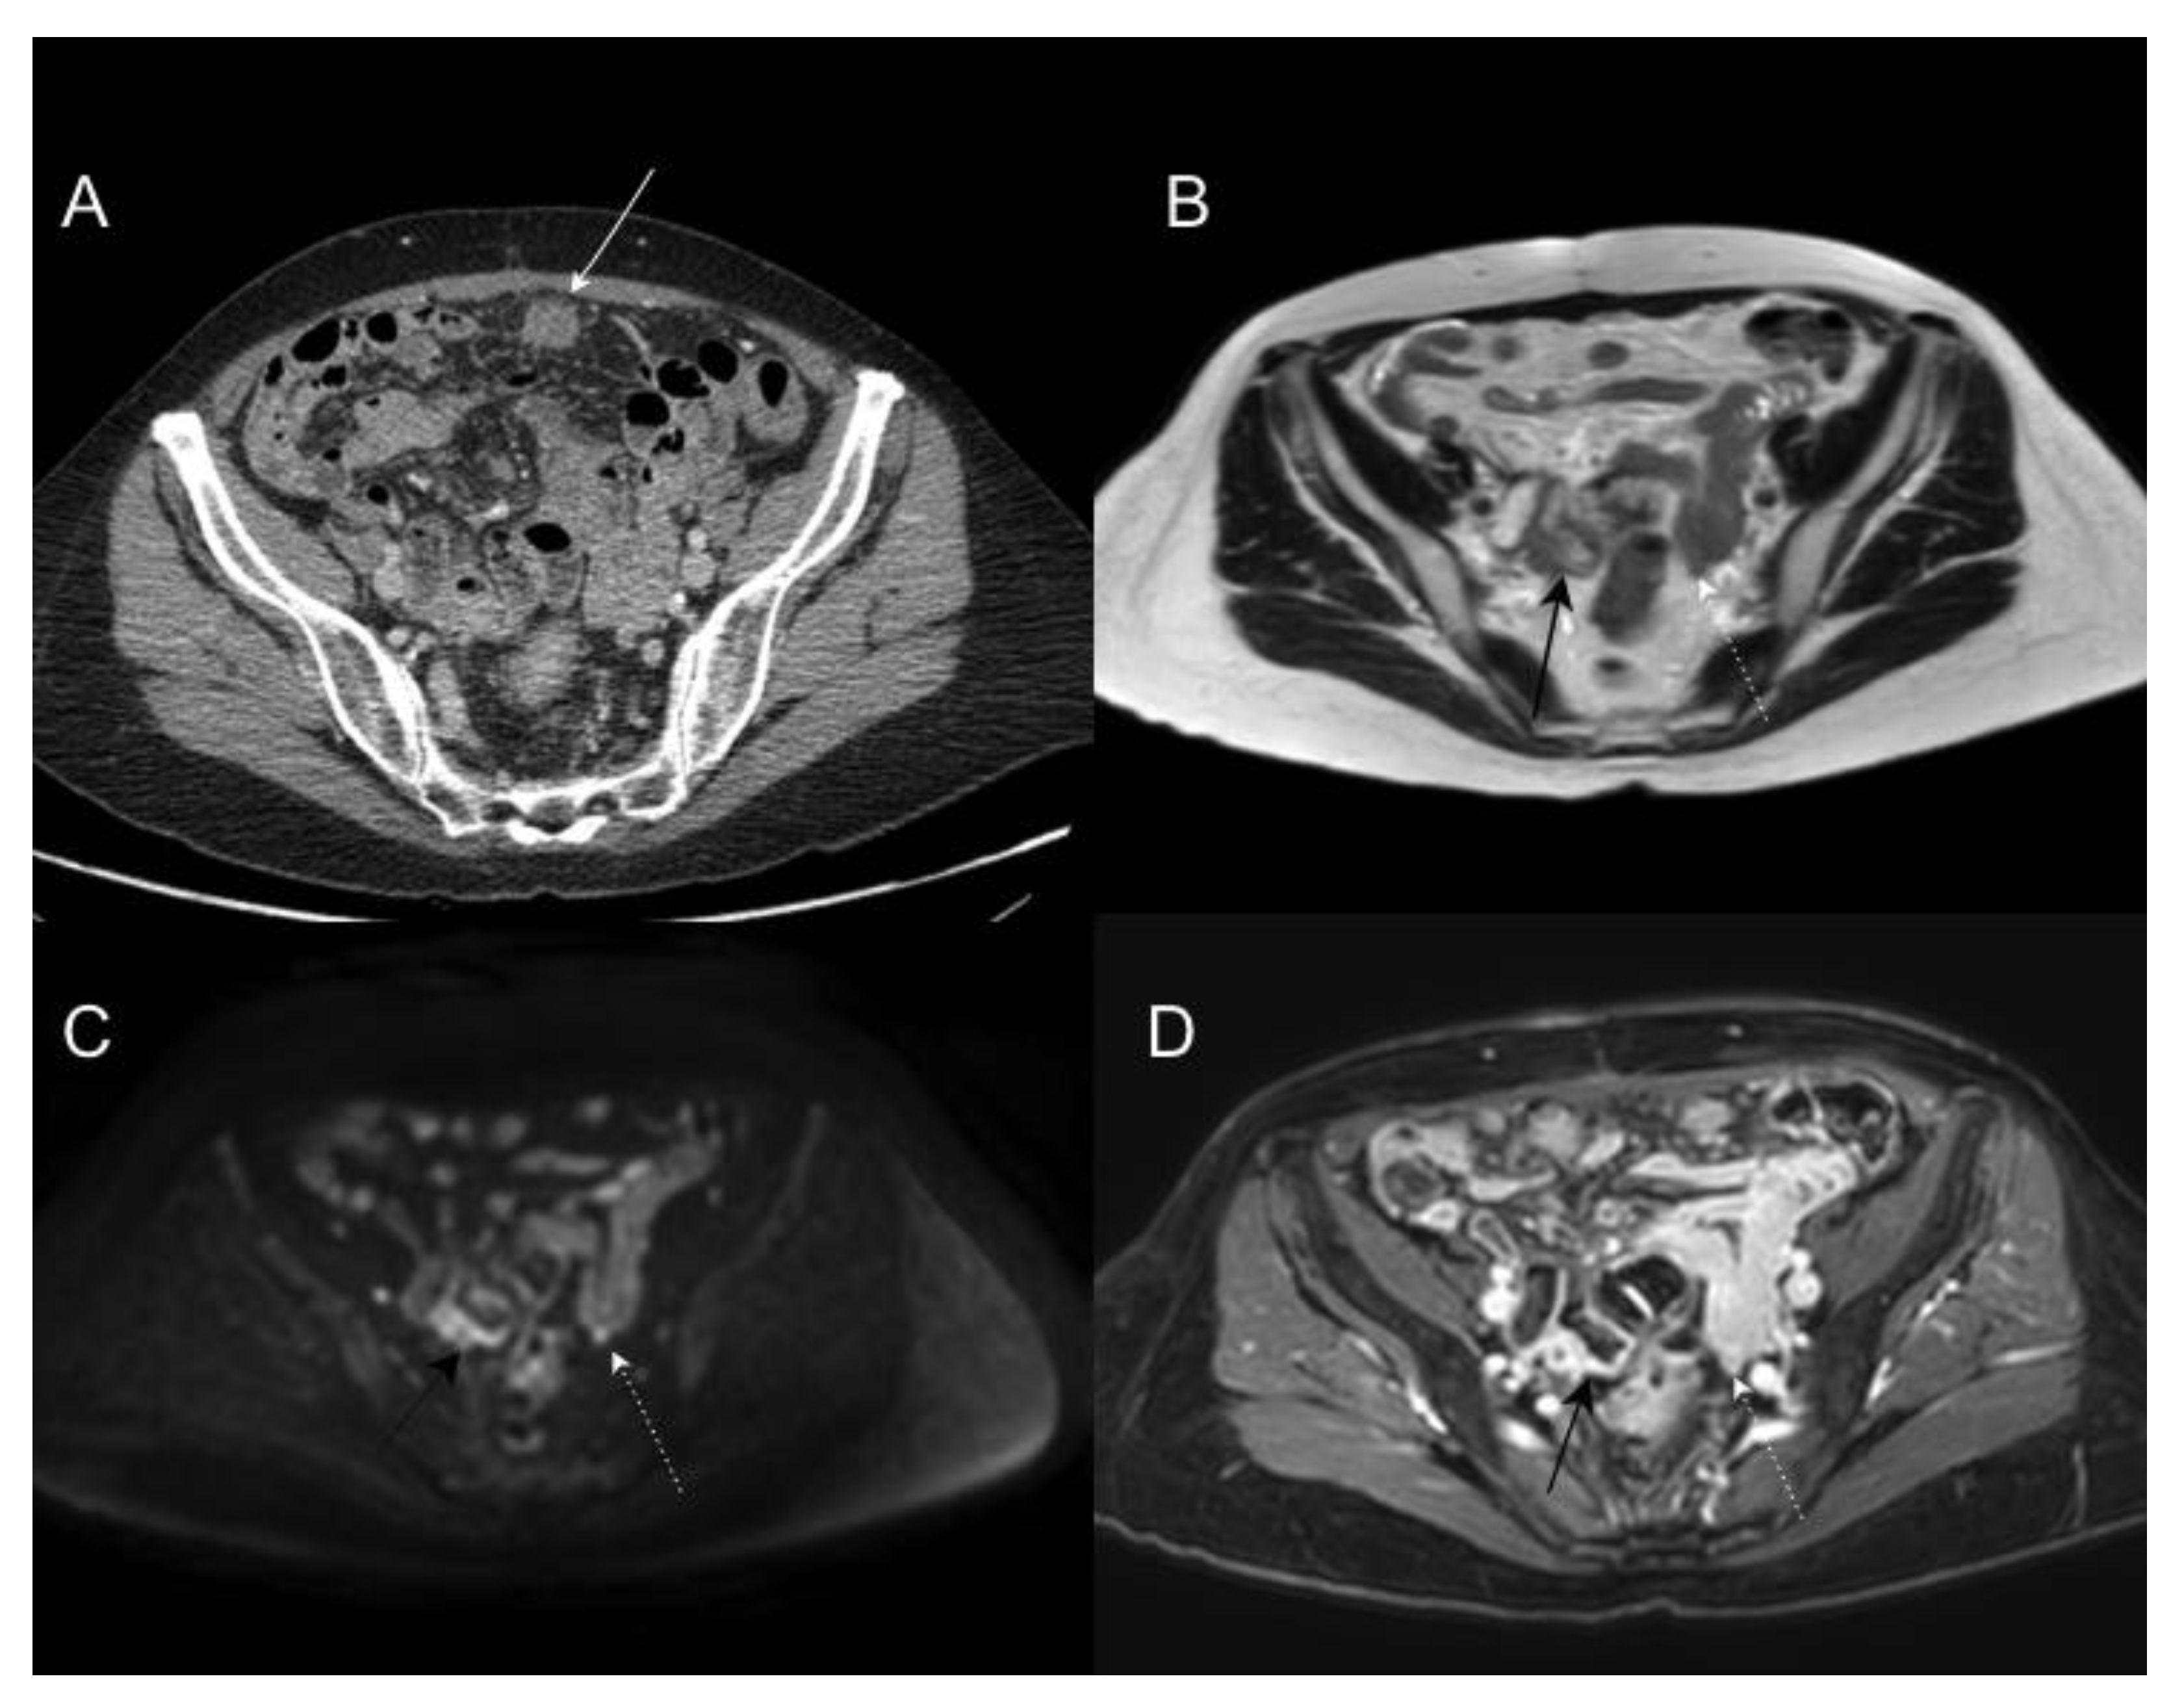

- De Vuysere, S.; Vandecaveye, V.; De Bruecker, Y.; Carton, S.; Vermeiren, K.; Tollens, T.; De Keyzer, F.; Dresen, R.C. Accuracy of whole-body diffusion-weighted MRI (WB-DWI/MRI) in diagnosis, staging and follow-up of gastric cancer, in comparison to CT: A pilot study. BMC Med. Imaging 2021, 21, 1–9. [Google Scholar] [CrossRef] [PubMed]

- Espada, M.; Garcia-Flores, J.R.; Jimenez, M.; Alvarez-Moreno, E.; De Haro, M.; Gonzalez-Cortijo, L.; Hernandez-Cortes, G.; Martinez-Vega, V.; Sainz De La Cuesta, R. Diffusion-weighted magnetic resonance imaging evaluation of intra-abdominal sites of implants to predict likelihood of suboptimal cytoreductive surgery in patients with ovarian carcinoma. Eur. Radiol. 2013, 23, 2636–2642. [Google Scholar] [CrossRef] [PubMed]

- Fujii, S.; Matsusue, E.; Kanasaki, Y.; Kanamori, Y.; Nakanishi, J.; Sugihara, S.; Kigawa, J.; Terakawa, N.; Ogawa, T. Detection of peritoneal dissemination in gynecological malignancy: Evaluation by diffusion-weighted MR imaging. Eur. Radiol. 2007, 18, 18–23. [Google Scholar] [CrossRef] [PubMed]

- Garcia Prado, J.; González Hernando, C.; Varillas Delgado, D.; Saiz Martínez, R.; Bhosale, P.; Blazquez Sanchez, J.; Chiva, L. Diffusion-weighted magnetic resonance imaging in peritoneal carcinomatosis from suspected ovarian cancer: Diagnostic performance in correlation with surgical findings. Eur. J. Radiol. 2019, 121, 108696. [Google Scholar] [CrossRef]

- Dresen, R.C.; De Vuysere, S.; De Keyzer, F.; Van Cutsem, E.; Prenen, H.; Vanslembrouck, R.; De Hertogh, G.; Wolthuis, A.; D’Hoore, A.; Vandecaveye, V. Whole-body diffusion-weighted MRI for operability assessment in patients with colorectal cancer and peritoneal metastases. Cancer Imaging 2019, 19, 1. [Google Scholar] [CrossRef] [PubMed]